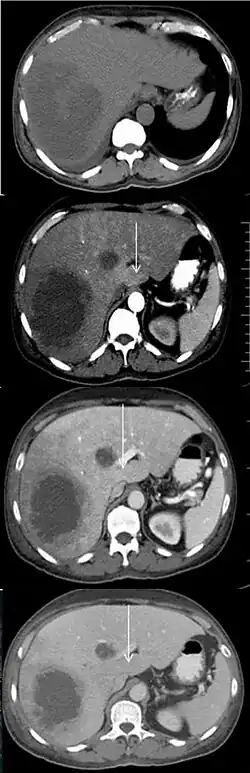

Transient hepatic attenuation differences

Transient hepatic attenuation differences (THAD) are areas of enhancement during the arterial phase of contrast CT of the liver. THAD is thought to be a physiological phenomenon resulting from regional variation in the blood supply by the portal vein and/or the hepatic artery. THAD may in some cases be associated with liver tumors such as a hepatocellular carcinoma.[2]